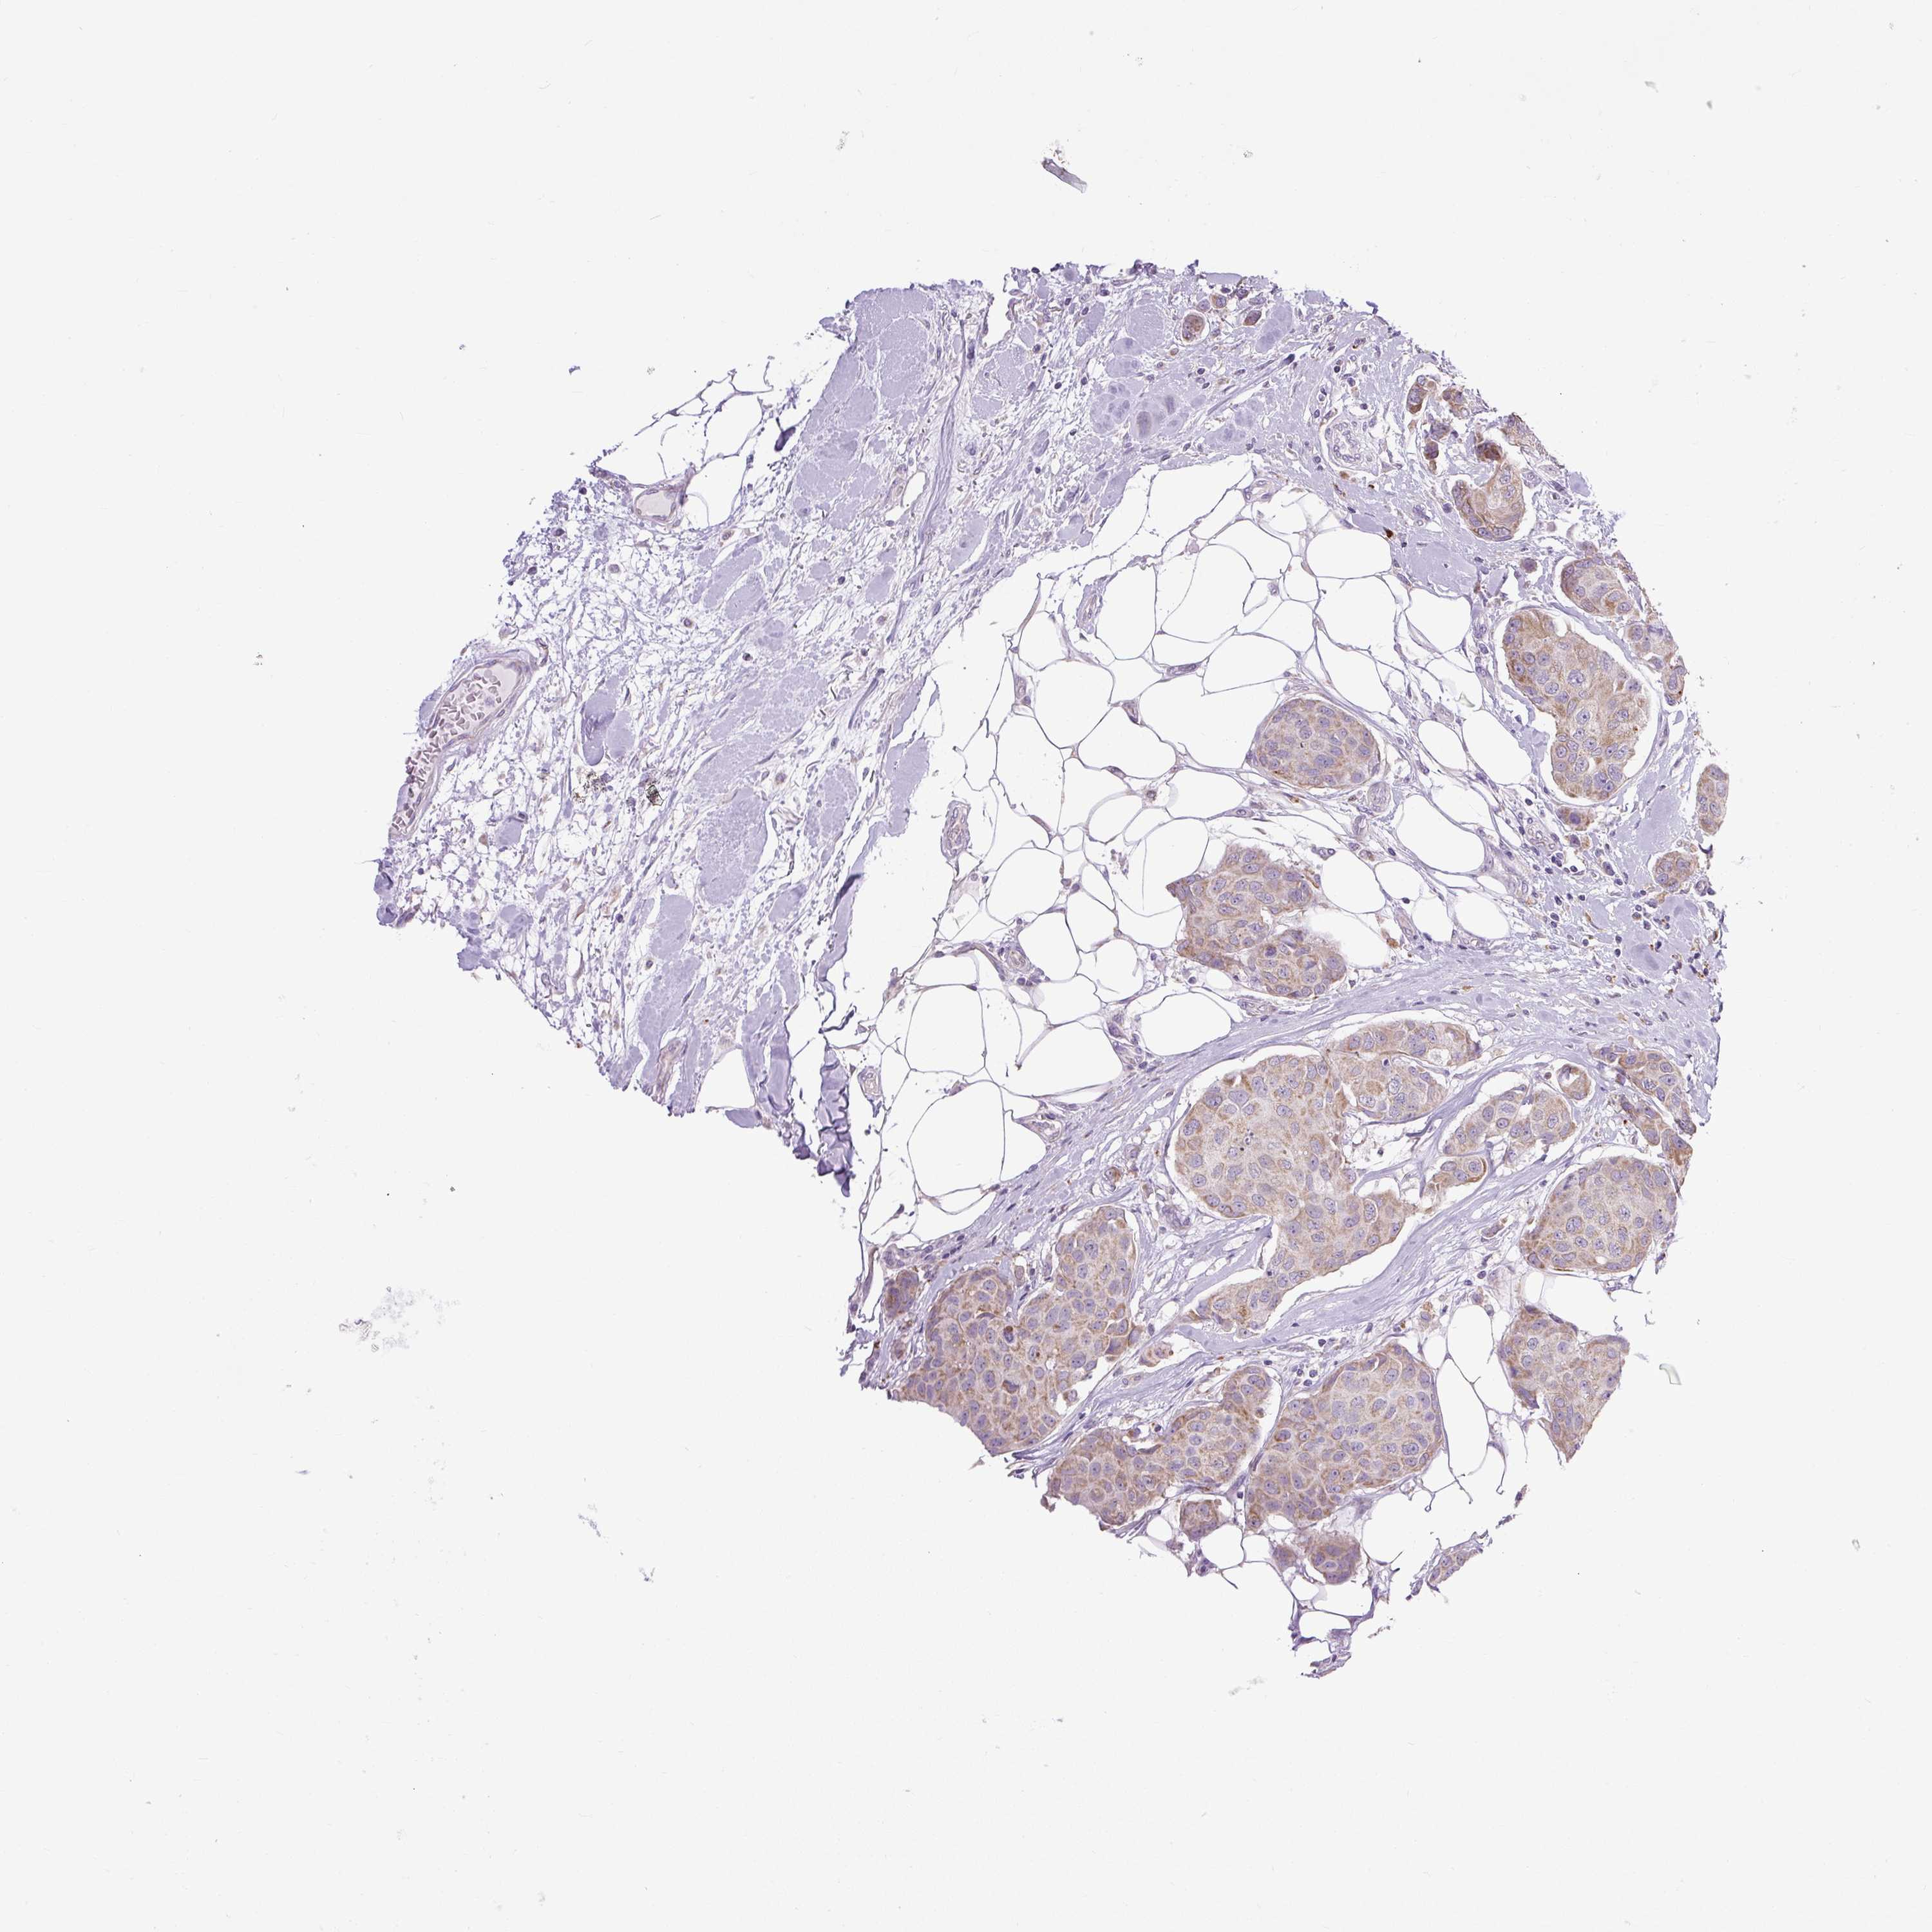

CANCER BREAST CANCER Show tissue menu

BRCA TCGA BRCA VALIDATION PROTEIN EXPRESSION